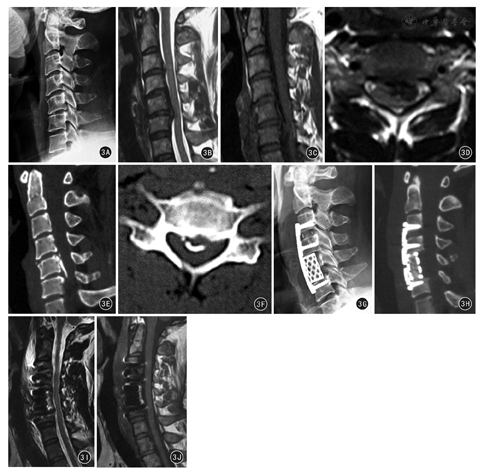

本组134例患者术后均获随访,随访时间6~36个月,平均(16.5±8.1)个月。术中发现37例患者韧带与硬脊膜无粘连,分离无硬脊膜破损;其余97例患者后纵韧带骨化物与硬脊膜粘连,在"安全减压间隙"下采用锐利神经剥离子成功分离92例,另外5例因骨化与硬脊膜融合一体,分离困难,在进行最大限度分离后,将骨化粘连的硬脊膜一起切除,术后发生脑脊液漏,其中术前CT横断面上椎管狭窄率30%~60% 1例,>60% 4例。4例经局部压迫并平卧3~5 d后脑脊液漏停止,1例顽固性脑脊液漏患者经反复穿刺抽吸并加压治疗1个月后愈合。本组无一例患者出现感染或者脊髓损伤。术后JOA评分8~16分,平均(14.9±2.7)分,与术前相比明显提高,差异有统计学意义(t=2.210, P<0.05)。术后1周JOA评分改善率41.6%~92.3%,平均82.1%±19.0%,其中疗效优70例,良49例,可15例,优良率88.8%。X线片定期随访发现植骨在6~ 12个月内融合,平均(7.1±0.9)个月。术后行颈椎MRI及CT检查,提示骨化物切除满意,硬膜囊及脊髓形态恢复良好。典型病例见图3。